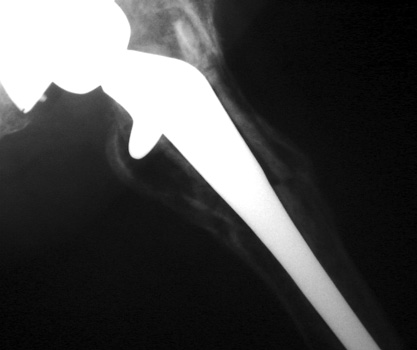

Cement fracture Gruen zone 6 close up next slide

CEMENT FRAGMENTATION

May occur with shift of femoral component.

Transverse fractures of cement near distal femoral stem seen in up to 1.5% of THR, associated with mild subsidence. If less than 4mm, usually not associated with failure. (Weber and Charnley)

CEMENT FRACTURE